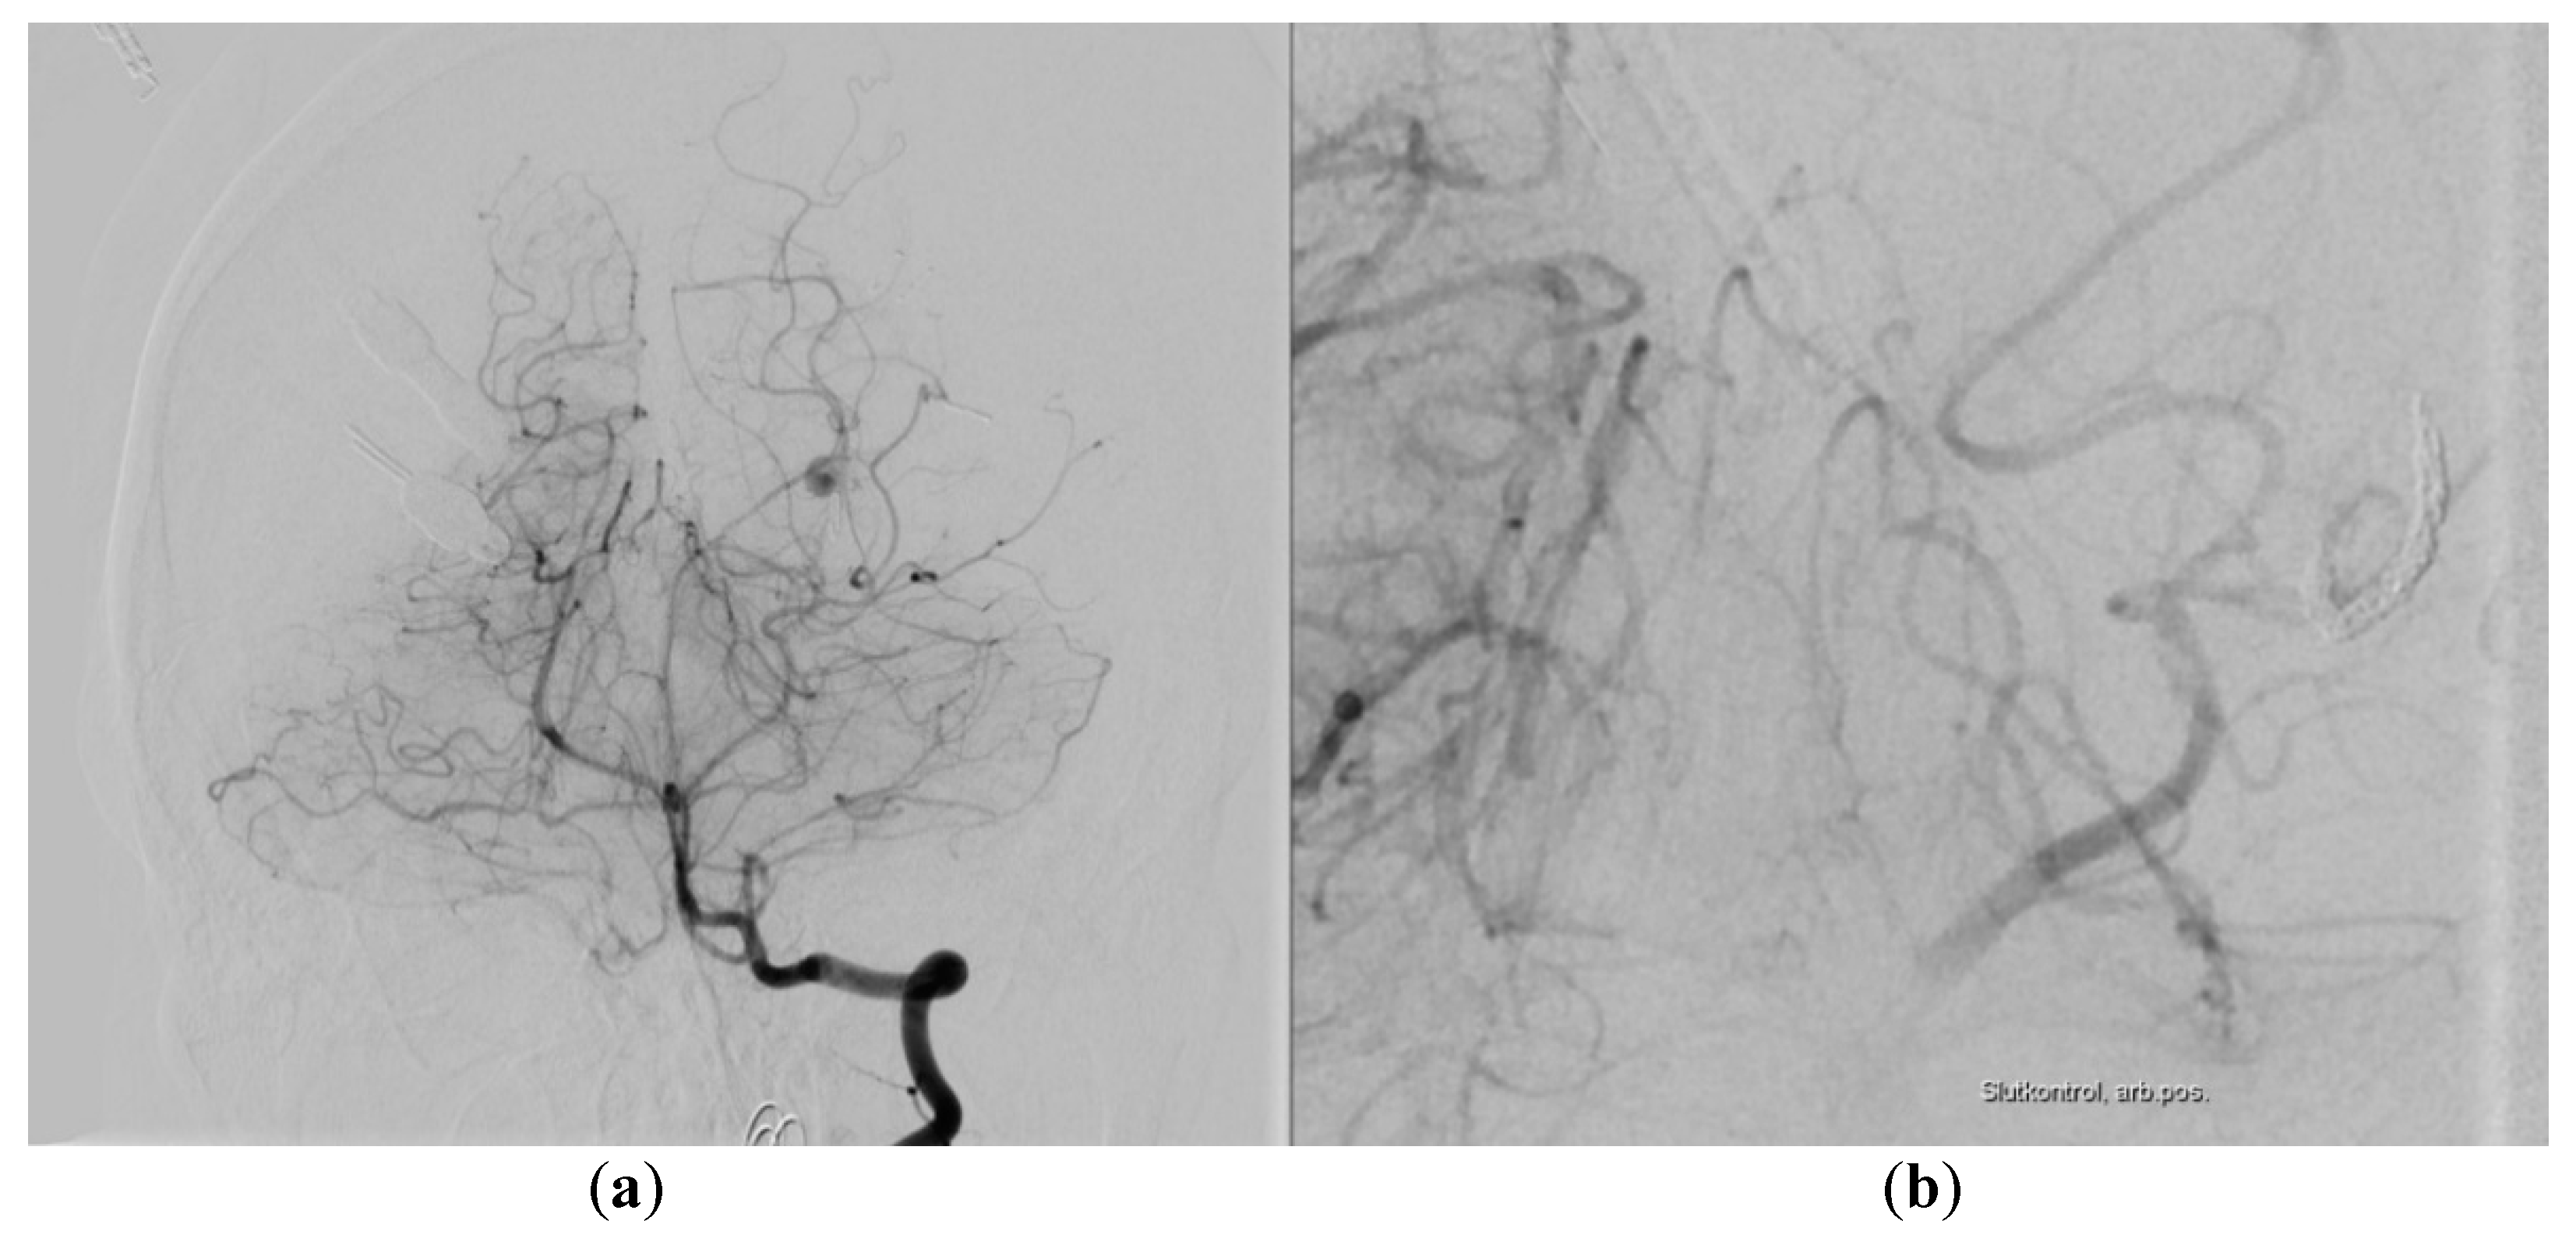

2. Case Report